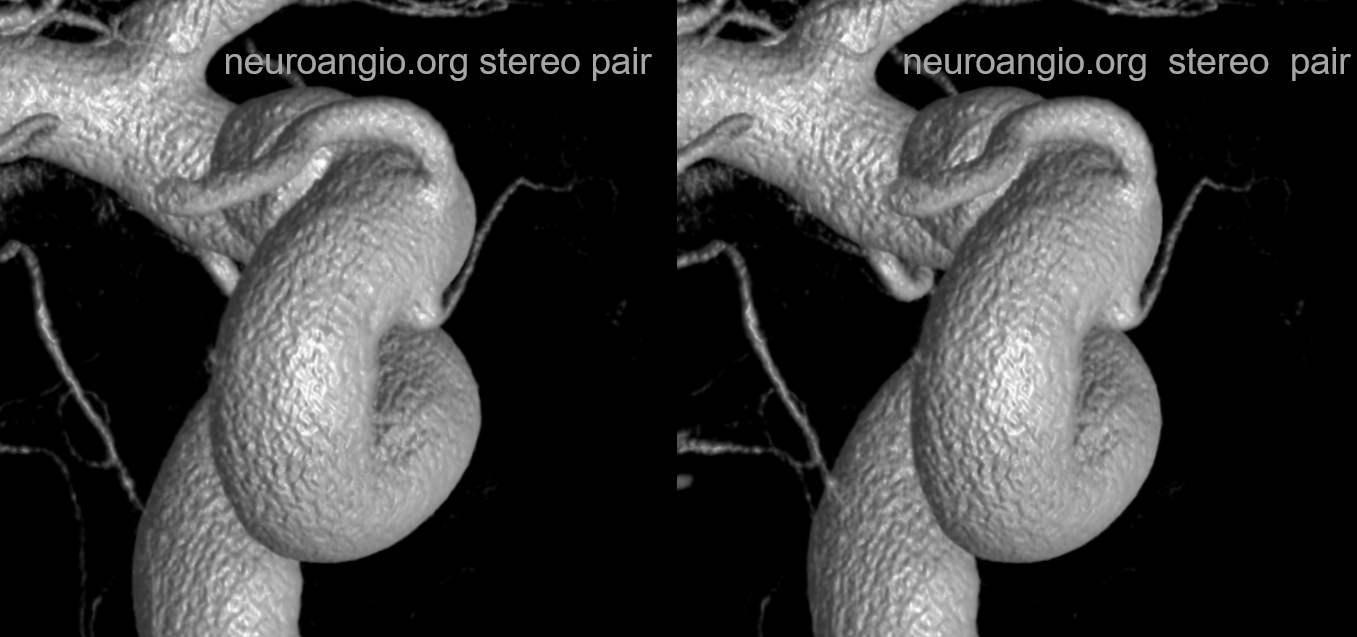

Stereos and MIPs. Both superior and inferior hypophyseals are well seen. The superior hypophyseal, despite being invisible on standard issue views, is quite large, even having two branches to the hypophysis.

Case courtesy Dr. Eytan Raz — here is a beautiful example of a very dominant superior hypophyseal artery (arrow) supplying the posterior hypophysis (arrowhead), with a correspondingly small inferior hypophyseal contribution from the MHT (dashed arrow)

Cross eye stereo

View from the back — again small inferior hypophyseal, big superior hypophyseal — balance again… See the beautiful vascular ring of the posterior pituitary — the connecting it with the contralateral side

Cross-eye stereo

MIP image shows the sella nicely — and helps prove its posterior pituitary

Pure arrowless images — easier to steal…

Of course, there is an aneurysm here — the branch point camp would point out how this larger than usual branch is a setup for aneurysmal formation. Naturally…